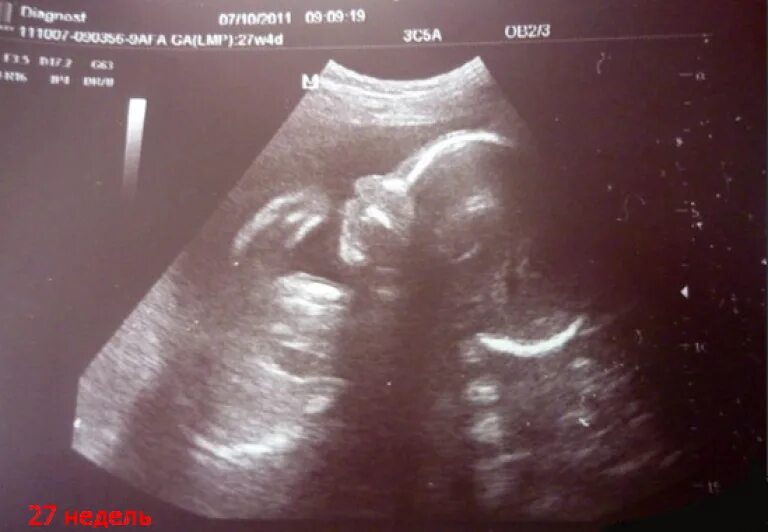

Ощущения 27 неделя